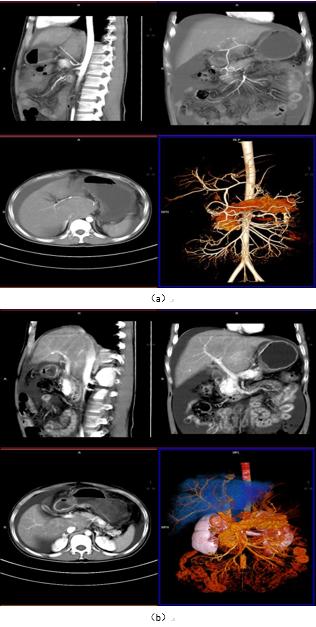

图 2-9 为肝脏 CT 一体化成像图,能更好的区分肝动脉、门脉、胆总管等结构,加上延迟扫描对正常组织器官及病变的显示影响有限,结合 3D 可视化图像,为临床医师手术提供精准化的参考、制定精准化的手术路径,为患者减少术后并发症。

图 2:一体化成像扫描肝动脉、门脉显像(VRT/MPR)

图 3:肝动脉显影(VRT/MIP)